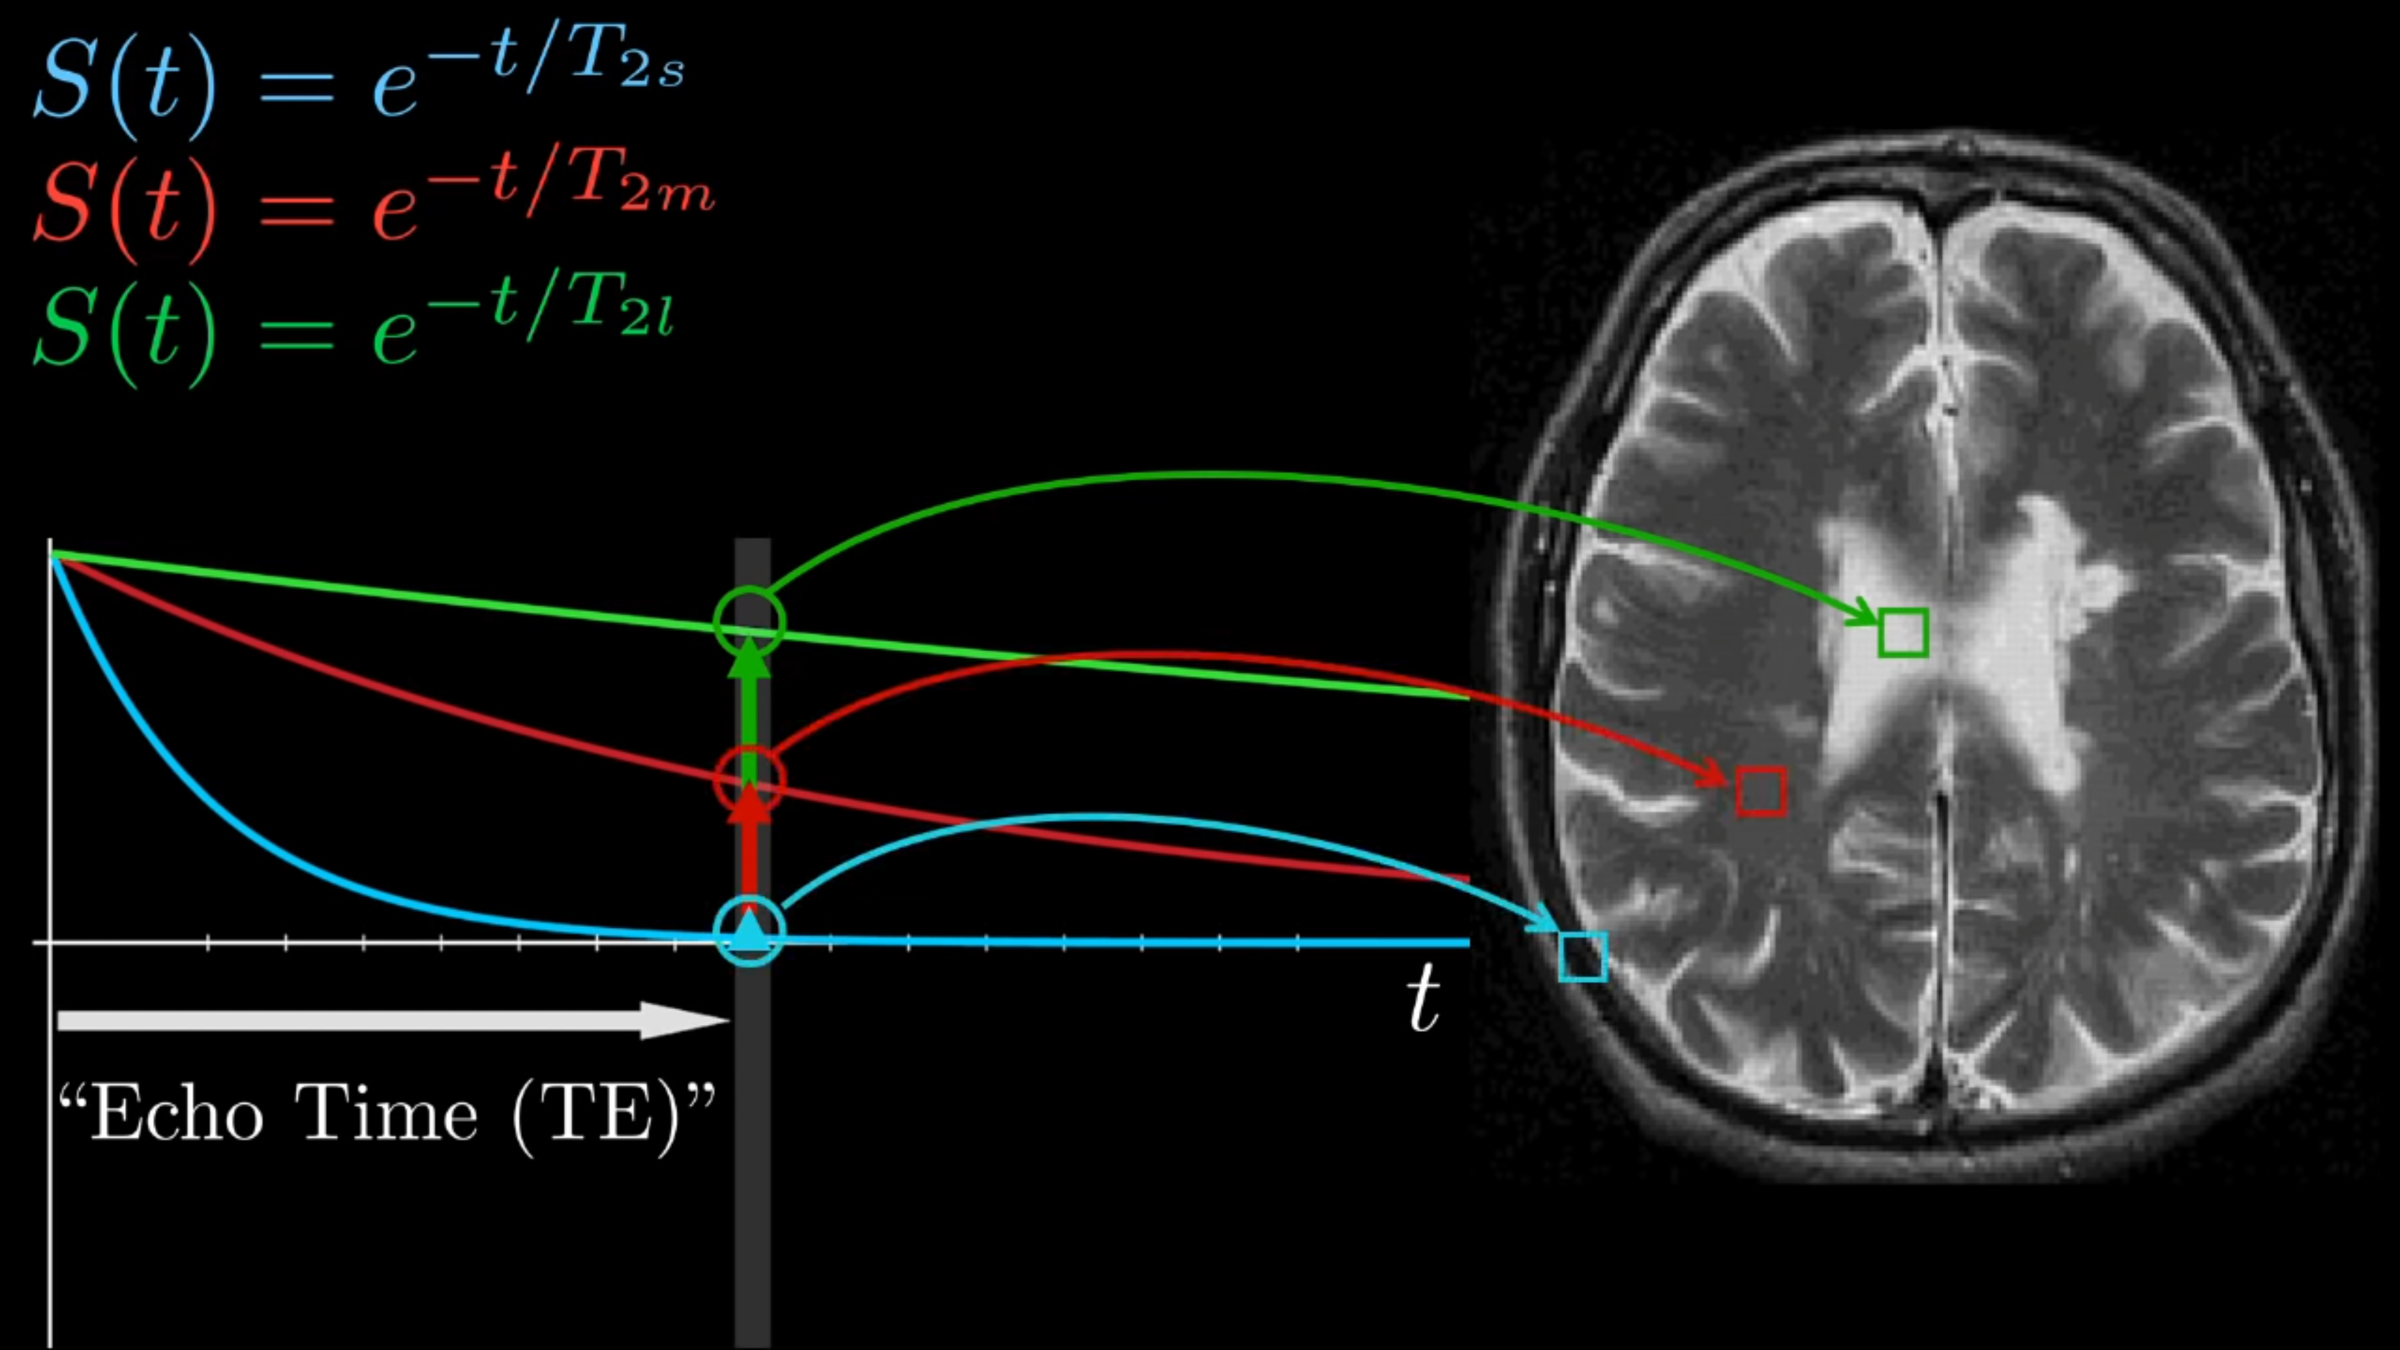

NMR

Signals

T2 tissue contrasting

T1 tissue contrasting

Obtaining an image.